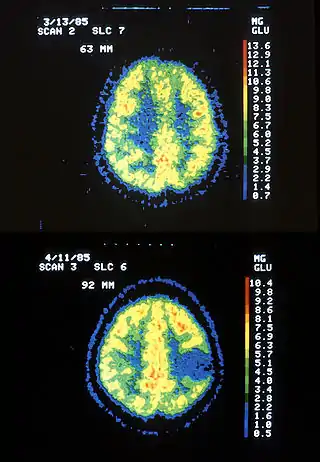

Imágenes por resonancia magnética de un paciente con astrocitoma, que muestran la progresión del tumor en el transcurso de siete años